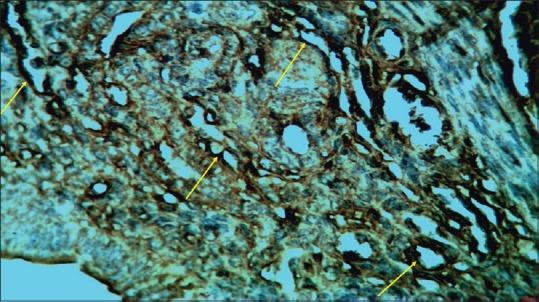

Endometrium angiogenesis in control group showed that mean ± standard deviation was 24.15 ± 11.15, gonadotropin group was 62.50 ± 24.16, and gonadotropin + progesterone group was 41.85 ± 19.54. Significant difference between the control group and gonadotropin group and between the control group and gonadotropin + progesterone was observed. Statistically significant differences were observed in all groups in the endometrial angiogenesis ( < 0.05).

Ovarian induction with gonadotropins and gonadotropins + progesterone could not change the morphometrically index of endometrial glandular epithelium in mice. Ovarian stimulation followed by progesterone injection could modify the angiogenesis of mice endometrium.

对照组子宫内膜血管生成情况显示,平均值±标准差为24.15±11.15,促性腺激素组为62.50±24.16,促性腺激素+孕酮组为41.85±19.54。观察到对照组与促性腺激素组之间以及对照组与促性腺激素+孕酮组之间存在显著差异。在所有组的子宫内膜血管生成中均观察到统计学上的显著差异(<0.05)。

用促性腺激素以及促性腺激素+孕酮进行卵巢诱导不能改变小鼠子宫内膜腺上皮的形态学指标。卵巢刺激后注射孕酮可改变小鼠子宫内膜的血管生成。